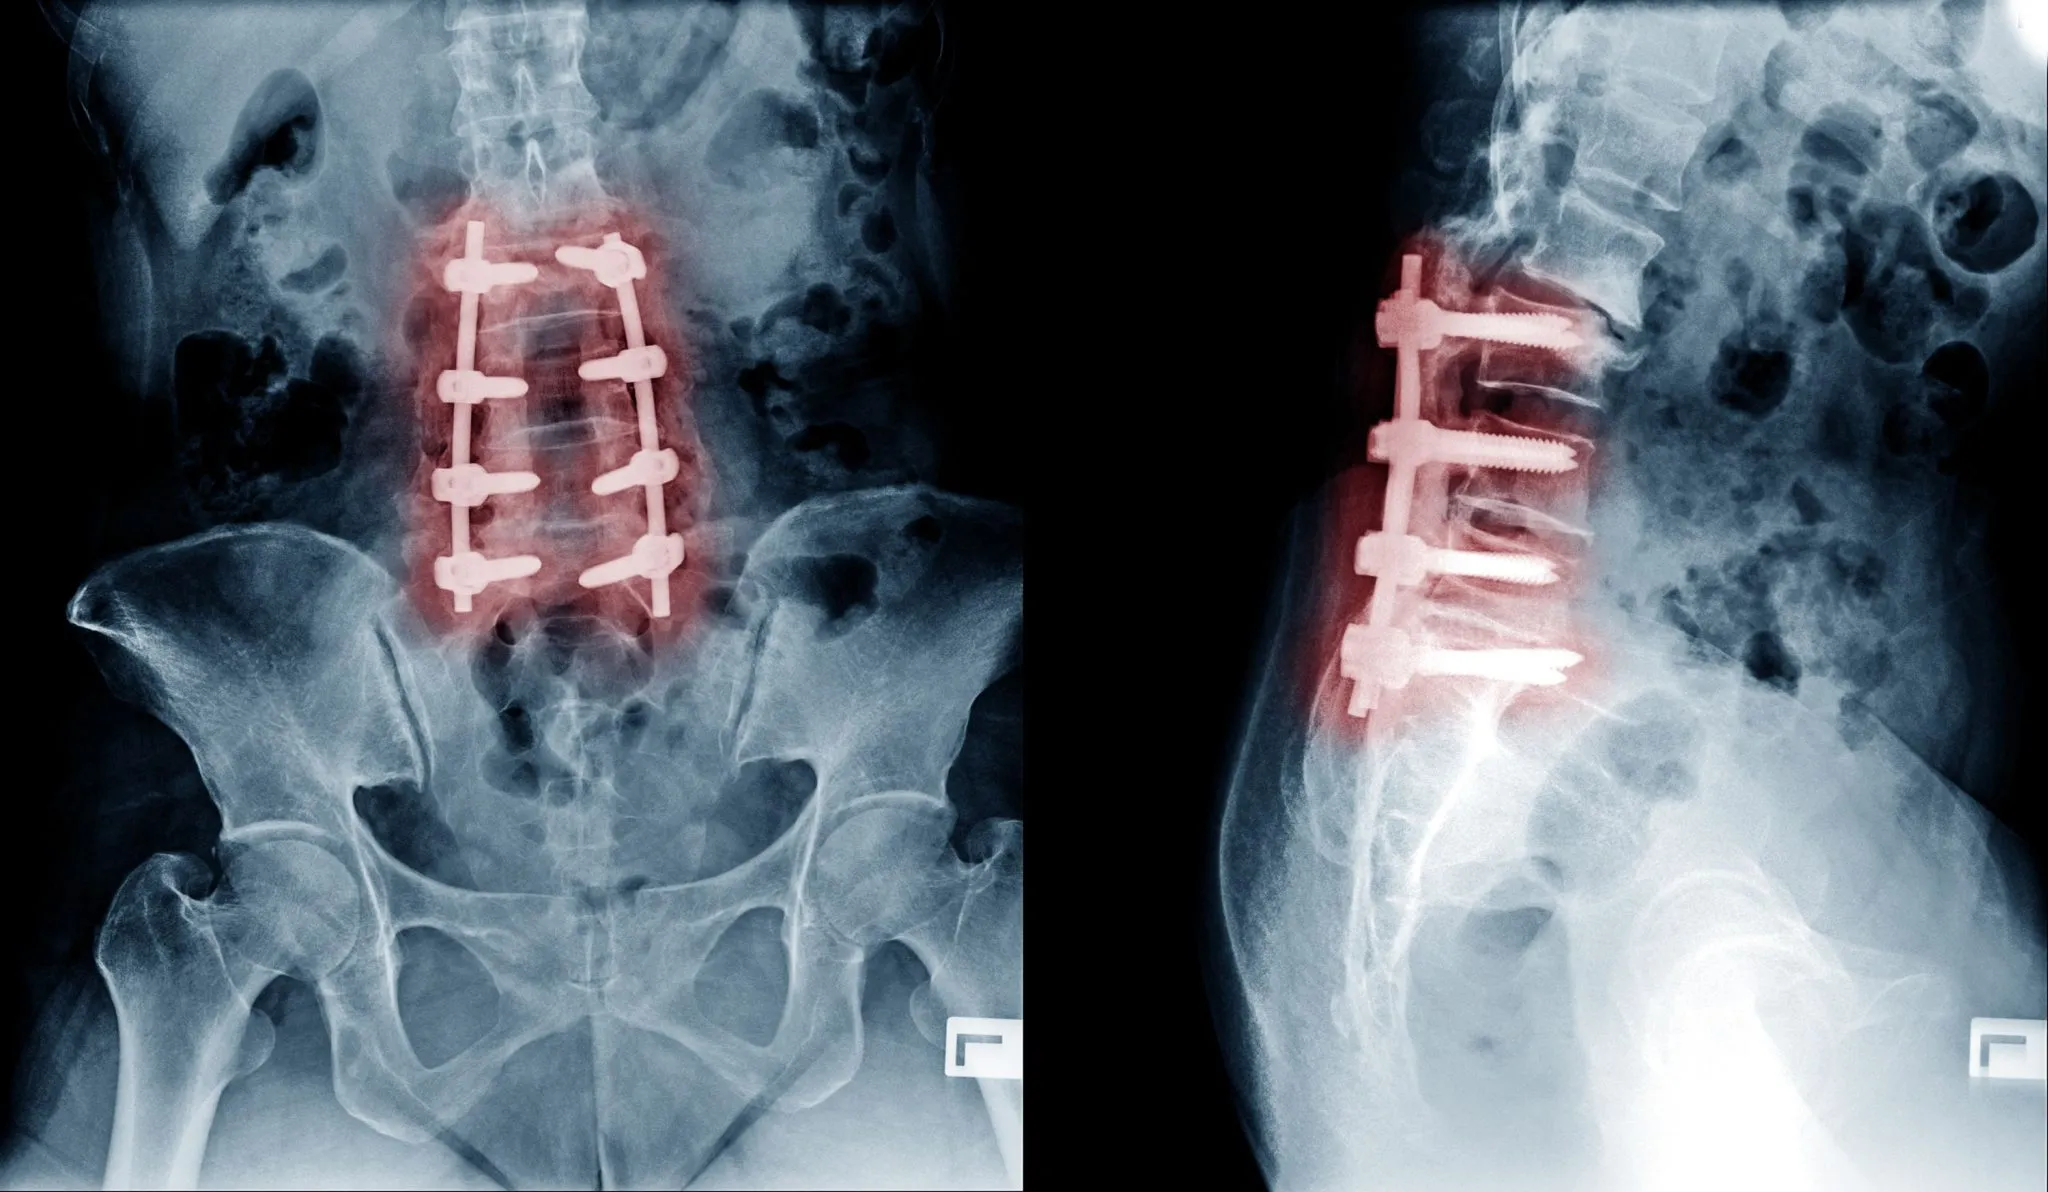

Spinal Fusion

Spinal fusion is a procedure used to stabilize the spine after decompression surgery or to correct spinal deformities. This surgery involves permanently joining two or more vertebrae using bone grafts, screws, or rods, eliminating movement at the affected segment.

While spinal fusion can work, it also limits spinal flexibility and increases stress on adjacent vertebrae, which may lead to adjacent segment disease.

Recovery from spinal fusion surgery is typically longer than other decompression surgeries, often requiring several months of healing and physical therapy to restore strength and mobility.